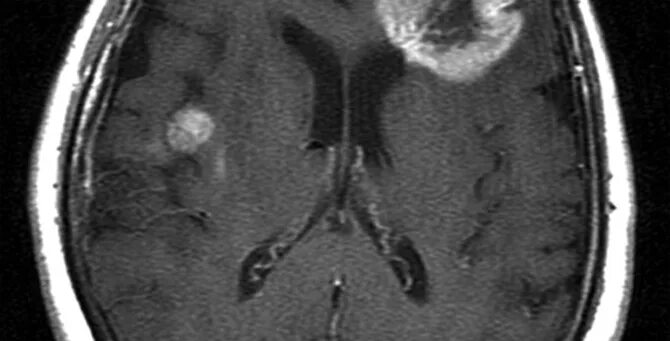

Рак неоперабельный 4 стадия